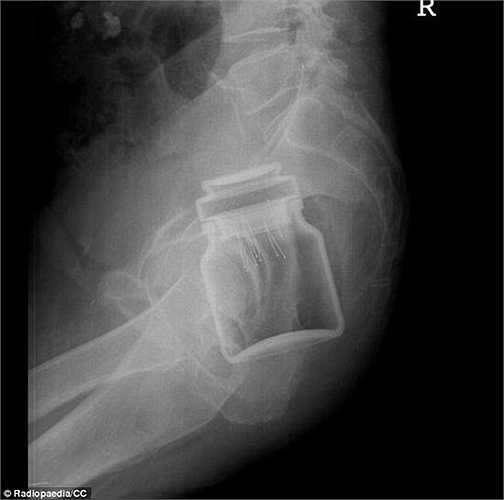

Bệnh nhân này quá đau bụng vì mắc kẹt bên trong là một lọ cà phê hòa tan nổi tiếng.